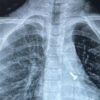

07 वर्ष के बच्चे के फेफड़े में फंसे पेंच को निकालकर एम्स के चिकित्सकों ने दिया जीवनदान

February 18, 2025ऋषिकेश: अखिल भारतीय आयुर्विज्ञान संस्थान, ऋषिकेश के पल्मोनरी मेडिसिन विभाग की ओर से संचालित ब्रोंकोस्कोपी प्रयोगशाला...